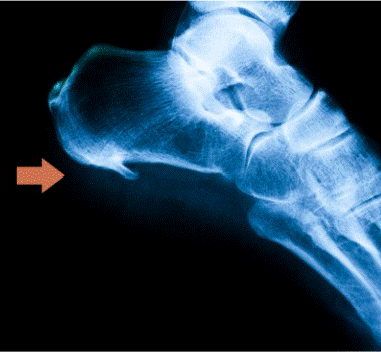

Lesión de la placa plantar y estabilidad metatarsofalángica

Introducción La lesión de la placa plantar es una causa frecuente de dolor en el antepié, especialmente en personas activas y corredores, y está estrechamente relacionada con la pérdida de estabilidad de las articulaciones metatarsofalángicas de los dedos menores. Se trata de una estructura clave para la función del antepié durante la fase de apoyo […]